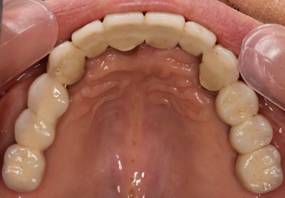

術後。上部構造はハイブリッドレジンです。しっかり嚙めるようになり喜んでいただきました。

上顎

下顎

上部構造装着後6年。ハイブリッドレジンを使用したため、少し艶がなくなってきました。上部構造の材料には金属、ハイブリッドレジン、セラミックなどがあります。セラミックはきれいですが欠けやすいため、最近はフルジルコニアを使っています。

上顎 少しすり減ってきました。

下顎。12か月に一度メインテナンスをしています。

インプラント装着後6年。順調に経過しています。12か月毎のメインテナンスをしています。